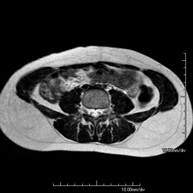

Prova diagnòstica no invasiva que consisteix en l'obtenció d'imatges d'alta definició anatòmica de la pelvis masculina mitjançant l'ús d'un camp electromagnètic i ones de ràdio (amb un emissor i un receptor). No utilitza radiació ionitzant. No requereix preparació prèvia. En algunes ocasions necessita l'ús de contrast paramagnètic (Gadolini) per caracteritzar les lesions. Aquesta prova permet valorar òrgans com la bufeta urinària, la unió entre els urèters i la bufeta, la pròstata, les vesícules seminals, la uretra i els ossos de la pelvis, entre d'altres. - RM de Fetge

Prova diagnòstica no invasiva que consisteix en l'obtenció d'imatges d'alta definició anatòmica de la glàndula prostàtica mitjançant l'ús d'un camp electromagnètic i ones de ràdio (amb un emissor i un receptor). No utilitza radiació ionitzant. S'utilitza una bobina endorectal per obtenir imatges de màxima definició anatòmica de la pròstata i permetre fer l'estudi espectroscòpic (estudi a nivell molecular que ajuda a diferenciar les cèl·lules d'origen maligne o tumoral). També es realitza l'estudi amb contrast paramagnètic, que aporta una millor definició tissular. Aquesta prova dura uns 40 minuts, durant els quals el pacient haurà d'estar el més quiet possible. Requereix una neteja del còlon com a preparació prèvia. Aquesta prova està especialment indicada en aquells pacients amb sospita de neoplàsia de pròstata, amb neoplàsia de pròstata coneguda per l'estadiatge tumoral, per a l'estudi de localització del tumor prostàtic com a guia o mapa per a la biòpsia, per al seguiment dels pacients amb neoplàsia de pròstata tractats amb tractament quirúrgic o radioteràpic, davant d'una sospita de reincidència de la neoplàsia de pròstata, etc. - RM de Cos sencer (Total body)